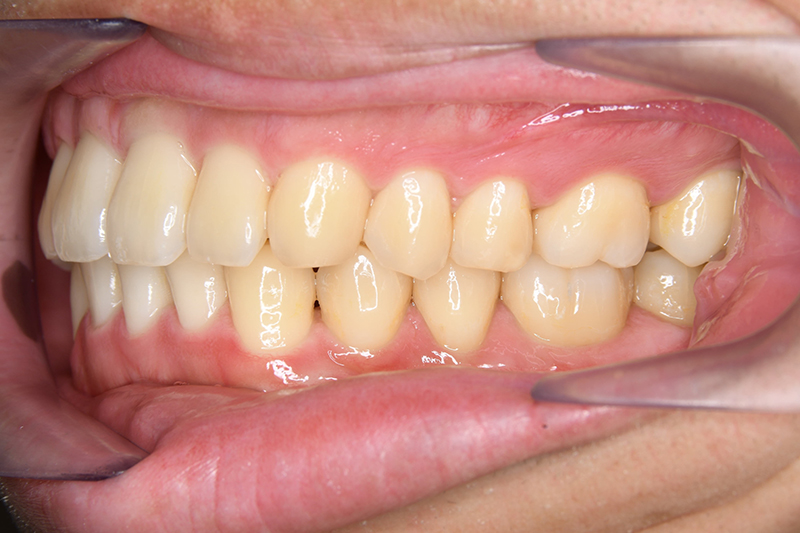

主訴 物が噛みづらい 診断名 下顎右側側切歯先天欠如を伴う過蓋咬合症例

口腔内所見 over jet 8.5mm、over bite 6.0mm、下顎前歯先天欠如、右側臼歯関係I級、左側II級(end on)、上顎歯列弓はオーボイド型なのに対して、下顎は狭窄歯列、叢生歯列弓を呈しており左側は鋏状咬合となっていた。